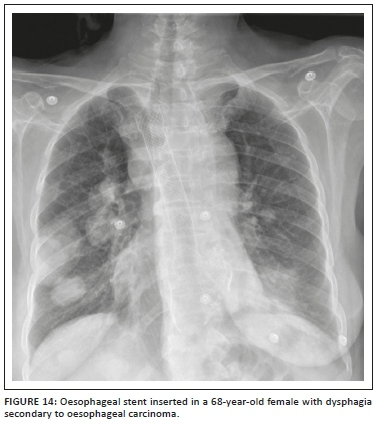

Medical devices and materials such as electrocardiogram (ECG) leads, ventilator tubing, syringes, clamps, temperature sensors, post-coronary artery bypass grafting (CABG) sternotomy wires, surgical clips, orthopaedic implants, gown snaps, etc. are commonly seen on CXRs. Because of its limited scope, we have not included cardiac devices in this article. However, there are other non-cardiac iatrogenic objects that can be seen on CXRs and these have been summarised in Table 2. Radiologists need to recognise them, be aware of their function and look for any related complications.